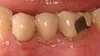

Fixed Bridges

Before: 3 Unit bridge with chipped porcelain molar (supporting metal showing on molar tooth), poor enamel color match to patient's natural teeth, and poor fit around the patient's gumline. After: Replaced Bridge with an All Porcelain Bridge. The new bridge now also matches the patient's natural tooth color and was designed to properly fit around the gumline. Proper fit aids in decreasing decay and the ease of the patient's ability to clean around a bridge.